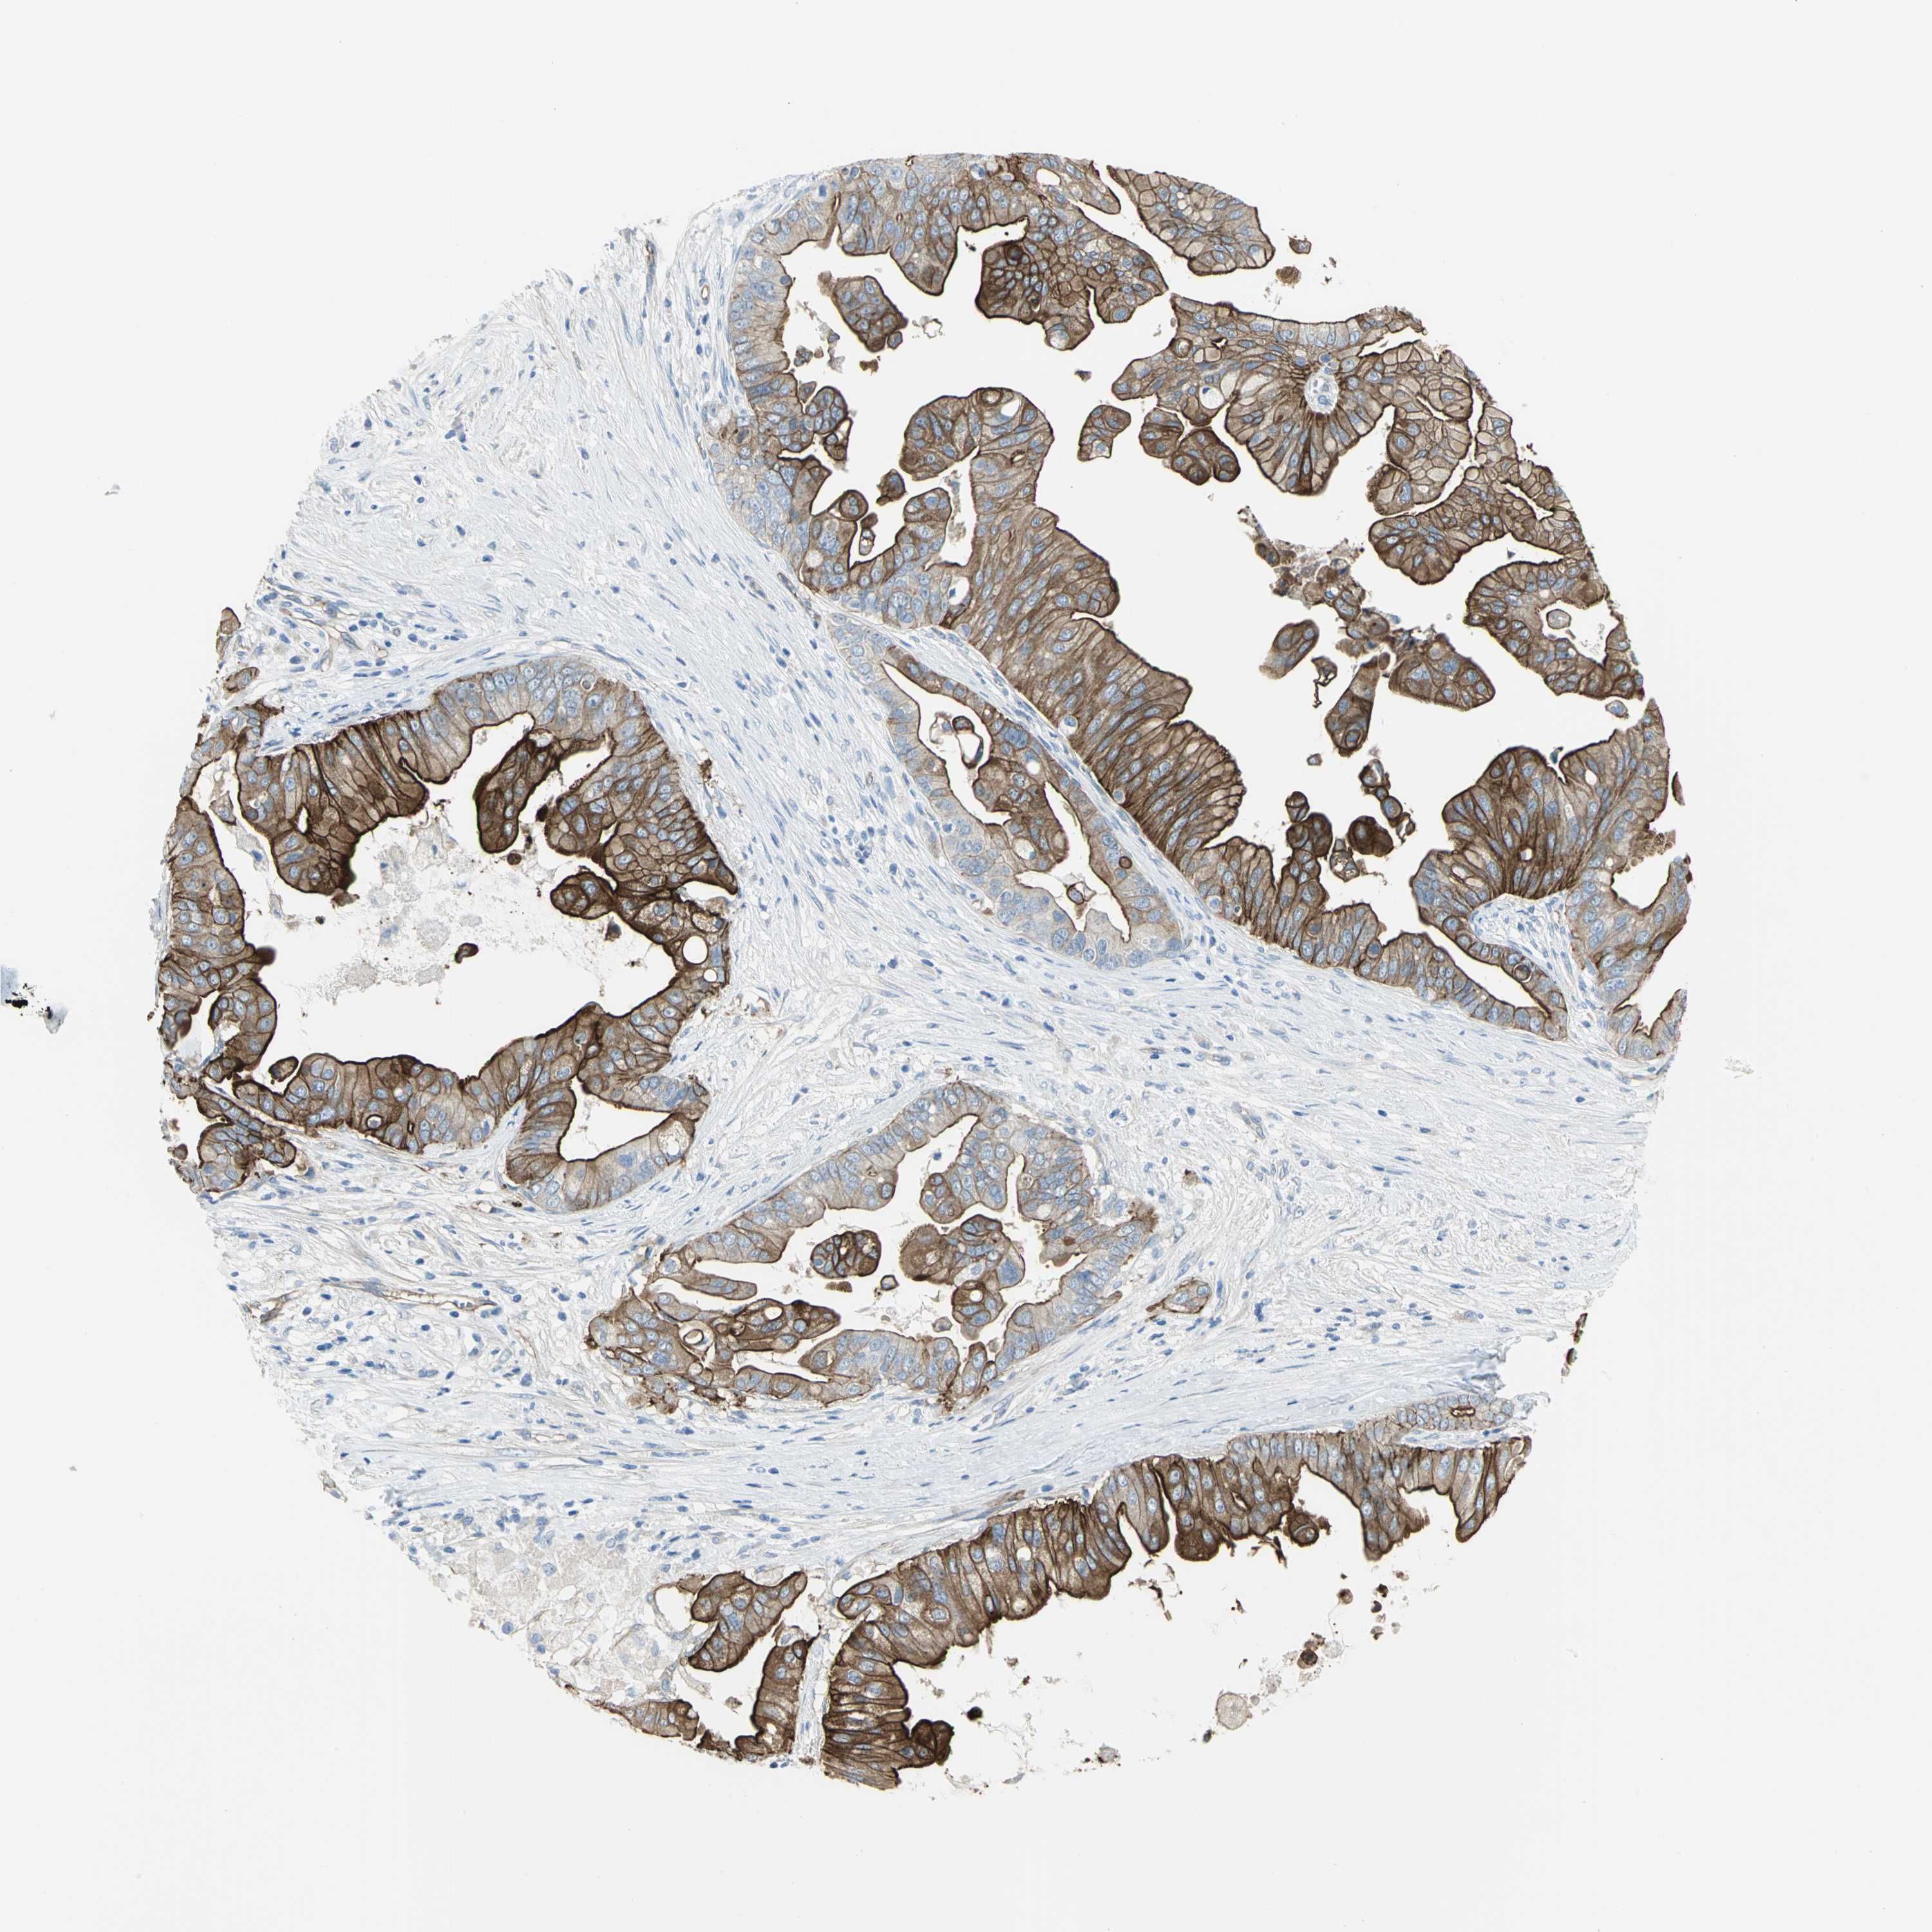

PANCREATIC CANCER - Protein expressioni

A mouse-over function shows sample information and annotation data. Click on an image to view it in a full screen mode. Samples can be filtered based on level of antibody staining by selecting one or several of the following categories: high, medium, low and not detected. The assay and annotation is described here.

Note that samples used for immunohistochemistry by the Human Protein Atlas do not correspond to samples in the TCGA dataset.

Antibody stainingi

Antibody staining in the annotated cell types in the current human tissue is reported as not detected, low, medium, or high, based on conventional immunohistochemistry profiling in selected tissues. This score is based on the combination of the staining intensity and fraction of stained cells.

Each image is clickable and will lead to virtual microscopy that enables deeper exploration of all samples and also displays staining intensity scores, fraction scores and subcellular localization as well as patient and tissue information for each sample.

Antibody HPA004747

Antibody CAB019322

High

Medium

Low

Not detected

Intensity

Strong

Moderate

Weak

Negative

Quantity

>75%

75%-25%

<25%

None

Location

Nuclear

Cytoplasmic/membranous

Cytoplasmic/membranous,nuclear

Adenocarcinoma, NOS